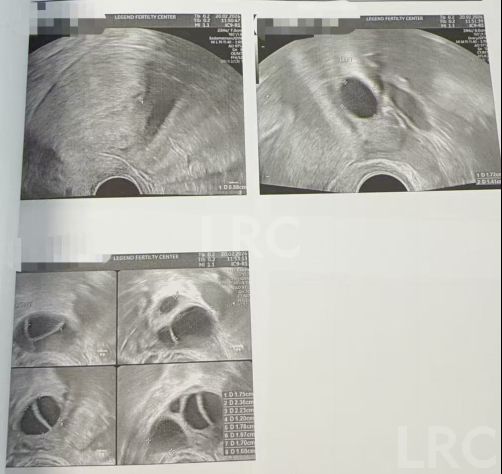

促排第八天

阴超检查:

- 右侧卵泡 5 颗 (17,16,14,13,12mm)

- 左侧卵泡 1 颗 (15mm)

激素水平检查:

- 促黄体生成素 4.18 miu/ml

子宫内膜厚度:5.36 mm

促排第十天

- 右侧卵泡 5 颗 (23,19,18,17,17,10mm)

- 左侧卵泡 1 颗 (16mm)

精细化个性化促排,盘活高龄稀缺卵泡资源:面对 X 女士 7-8 颗基础卵泡、左侧卵巢萎缩、FSH 异常高的难题,颂宝医生团队没有采用 “一刀切” 的常规促排方案,而是根据其身体状况、激素水平和卵泡发育特点,定制专属促排 + 调理方案。全程通过卵巢三维成像精准监测每一颗卵泡的发育轨迹,结合激素数据动态调整诊疗策略,让原本发育不均的稀缺卵泡,最终成功发育为 6 颗优质成熟卵泡,实现了 “少卵泡巧利用” 的诊疗目标,充分体现了 LRC 在高龄卵巢功能减退诊疗中的精准把控能力。